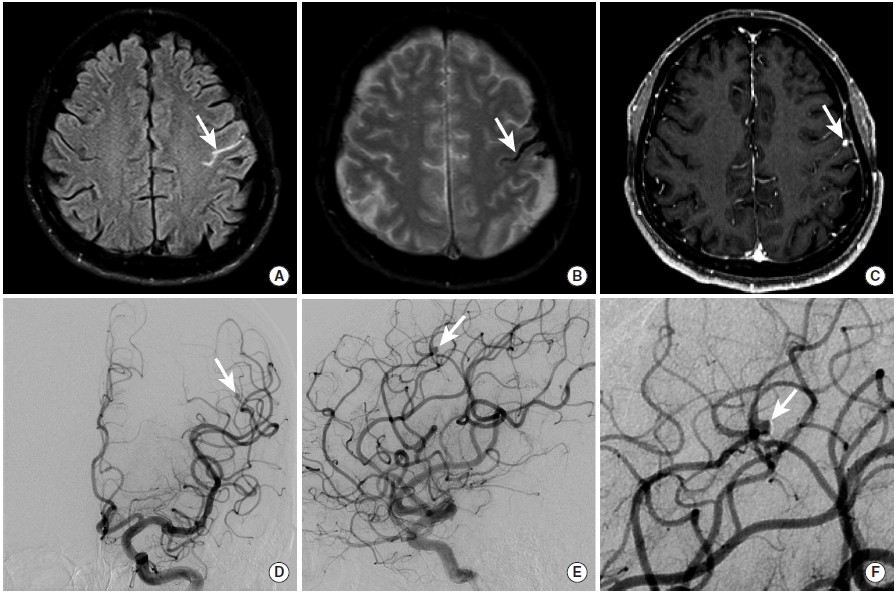

图16

中年女性,主要症状为头痛,后证实为继发于脑动脉血管炎的蛛网膜下腔出血。

图A:MRI的FLAIR成像可见右缘沟内的异常高信号(长尾箭头)。

图B:GRE序列进一步证实了脑沟内异常低信号,为蛛网膜下腔出血(长尾箭头)。

图C、D: DSA显示右侧大脑中动脉M4段(长尾箭头)和右侧大脑前动脉远端(未示出)微小的串珠样改变,与血管炎表现一致。